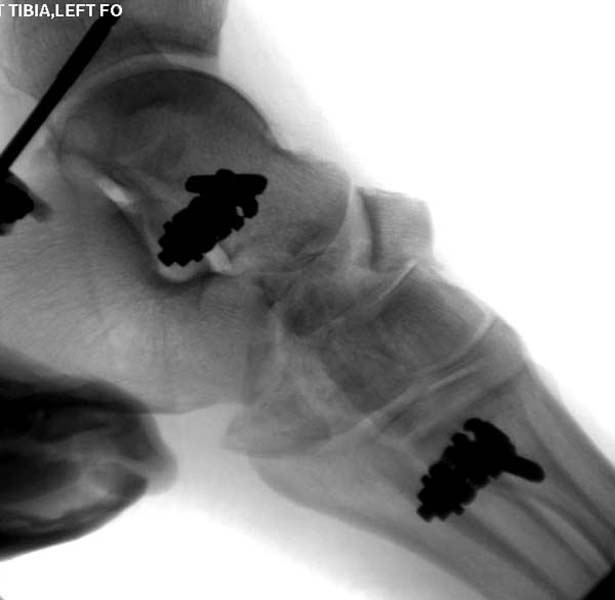

Через три дня повторная I&D, где через рану манипулировали дистальным фрагментом с установкой пары межфрагментарных шурупов. На рану вакуум и следующая обработка закончилась закрытием раны. Отек держался немного дольше, чем обычно.

После спадения отека вариантов фиксации много, включая мининвазивную технику, но данный случай закончили установкой простого аппарата Илизарова.